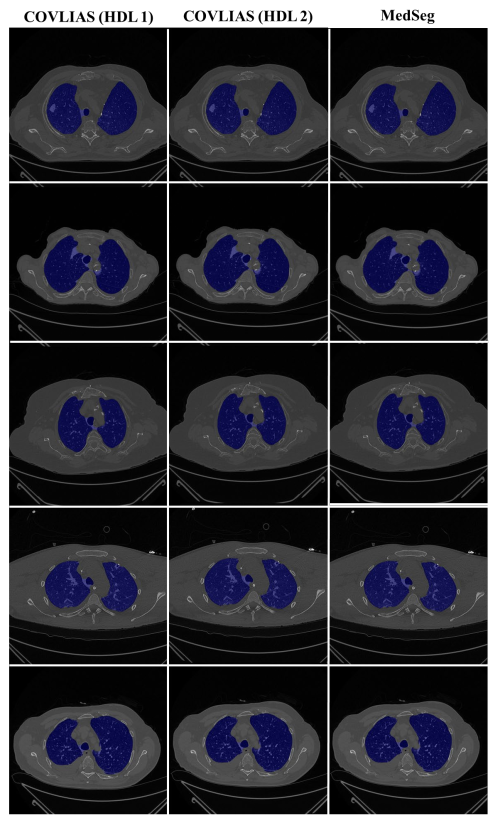

4.1. Performance: COVLIAS vs. MedSeg